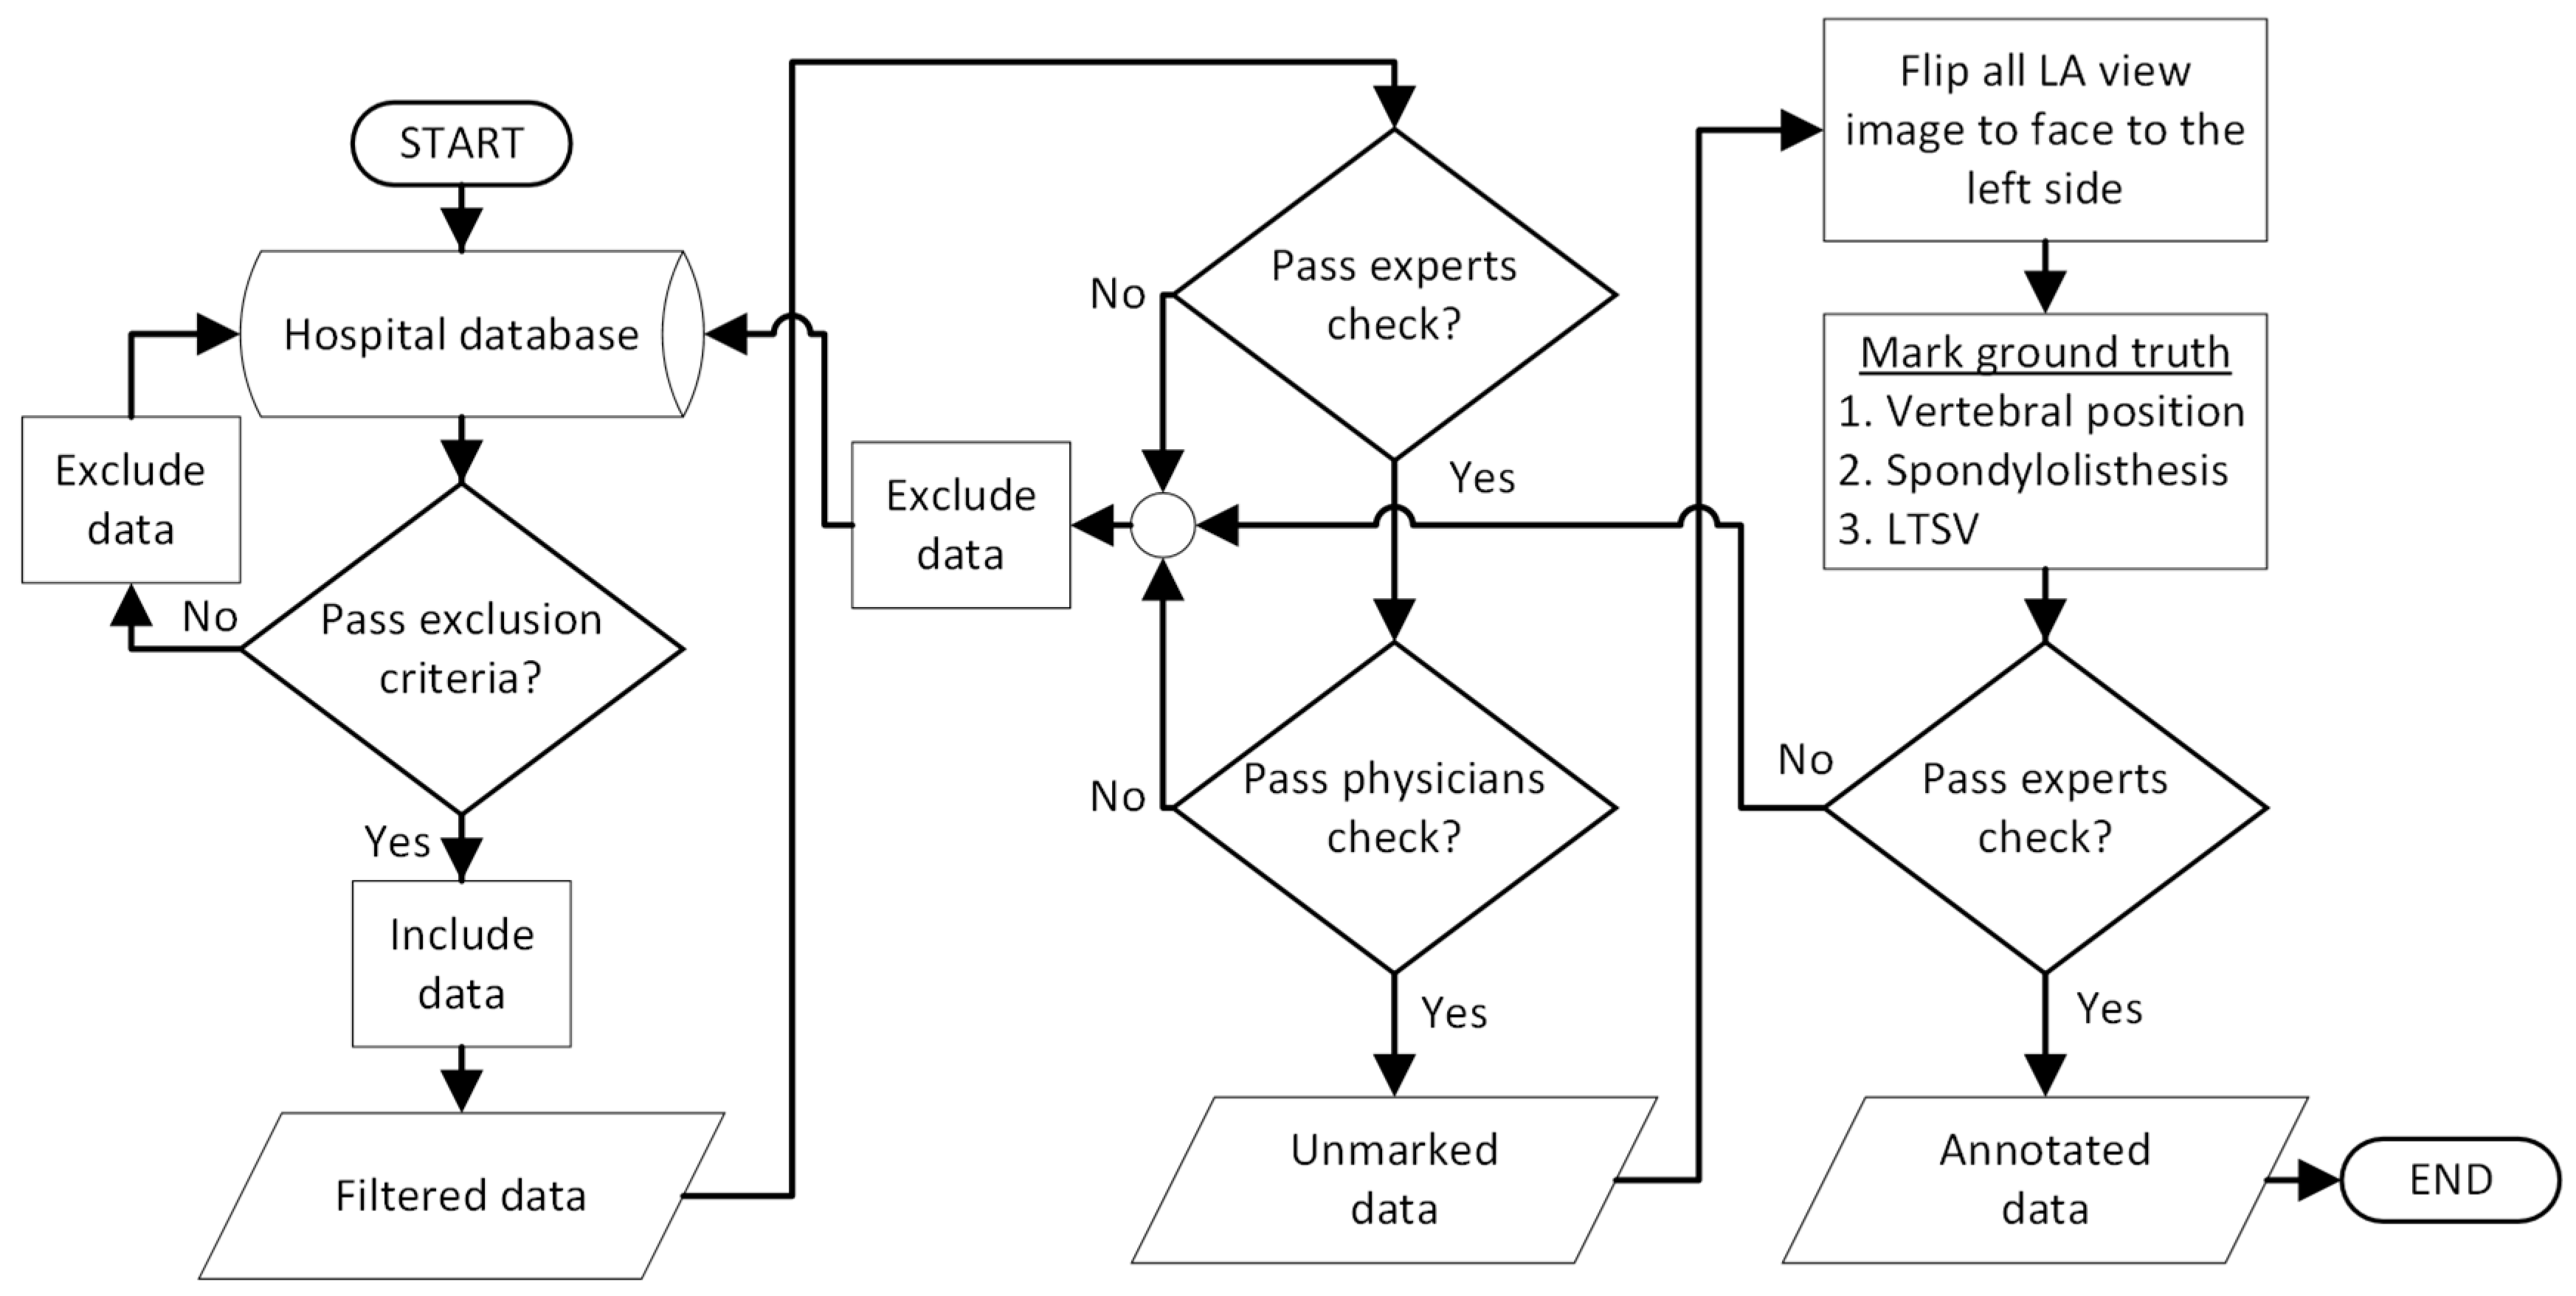

2.1. BUU-LSPINE

2.2. Ground Truth Data